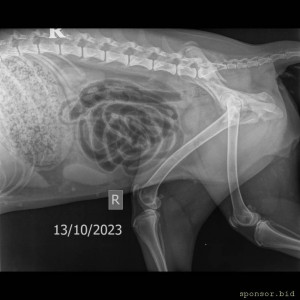

На втором снимке видно как раздроблена кость

Мою собаку сбила машина - Скелет средний 10-25 kg-Грудной-поясн. отд. LAT-13.10.2023-15_31_37-450.JPEG